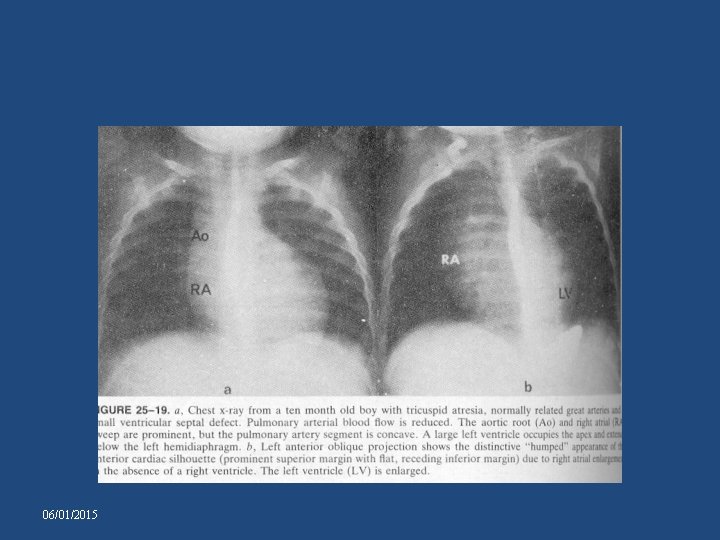

CHEST X-RAY-TA WITH NRGA AND SMALL VSD • • • Pulmonary vascularity reduced. Pulmonary artery segment – inconspicuous. Heart size – normal. Aorta prominent Right cardiac border: distinctive and prominent , accentuated by absence of RV. • LAO – Humped appearance of right cardiac border and a prominent left cardiac silhouette 06/01/2015

06/01/2015

TA with complete transposition and no obstruction • • Lungs – plethoric LV, LA, RA – enlarged Prominent apex formed by LV Right cardiac border seldom has distinctive hump-shaped contour – RV is relatively well developed • narrow vascular pedicle 06/01/2015